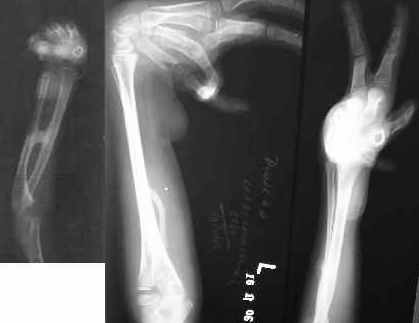

Etiology: Post burns contractures of the hands and the wrists Time elapsed since episode: 9 months In frame time: 7 weeks follow up after 4 years (his son had a compound supracondylar femoral fracture and he brought him to us for treatment from approximately 1600 kms away!)